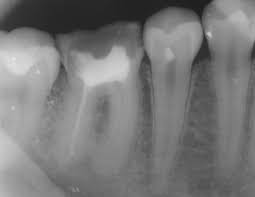

An endodontist is a specialized dentist who helps you in maintaining your teeth and gums by performing endodontic therapy. Endodontic therapy, popularly called root canal treatment, is a sophisticated dental/dentistry procedure entailing the removal of infected root canal (tooth pulp) tissue comprising nerve fibers and blood vessels. The word endodontic is a portmanteau of the Greek words ‘endo’ (inside) and ‘don’t’ (tooth).

Nearly 95% of those who visit our office with an endodontic issue, complain about agonizing tooth pain. However, we face a stiff challenge in pinpointing the root cause of a toothache. Nevertheless, in most cases, tooth pain occurs because of decay, cavity, and deep-seated infection that affect the innermost layer of a tooth (pulp tissue).

A myriad network of blood vessels and nerve fibers in the oral cavity not only encompasses the teeth and the gums but also extend to the peripheral vital organs. It is for this reason you experience pain over a large area of the dentine though the ache originates from the diseased or damaged teeth. Sometimes, the pain spreads to the ear, neck, or head.